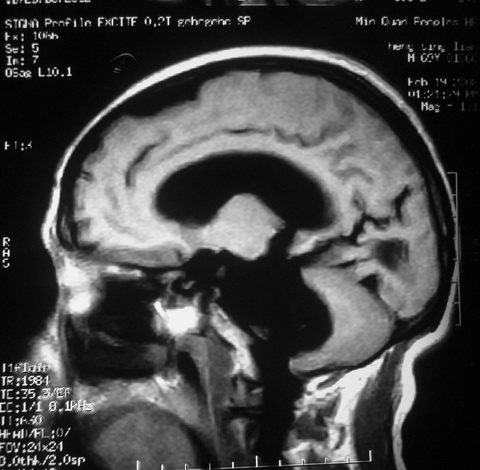

m,72,头疼,头晕两年,伴视力模糊三月,饮食呛咳两天。pe:颈部抵抗,左眼突出,左眼瞳孔约3mm,对光反射消失,双眼失明,伸舌困难,双肺呼吸音粗,心率110次/分,左上肢肌力i级,左下肢屈曲,肌张力高。现有08年2月19mri平扫及10年2月8日mri增强请会诊。ct病灶呈低密度伴散在点、片状等密度区,无明确钙化(无ct片资料可供上传)。[

左侧桥小脑区占位伴梗阻性脑积水----考虑 1神经鞘瘤 2室管膜瘤。

左侧桥小脑区神经鞘瘤伴梗阻性脑积水。

左侧桥脑小脑角区肿瘤并脑积水,考虑听神经瘤,脑膜瘤?

左侧桥脑小脑角区肿瘤并脑积水,考虑听神经瘤,